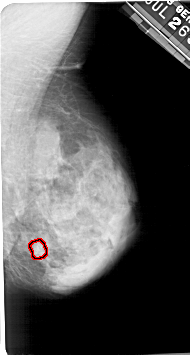

A_1185_1.LEFT_MLO

LEFT_MLO LINES 5491 PIXELS_PER_LINE 3166 BITS_PER_PIXEL 12 RESOLUTION 43.5 NON_OVERLAY

FILE: A_1185_1.RIGHT_MLO.OVERLAY

TOTAL_ABNORMALITIES 1

ABNORMALITY 1

LESION_TYPE CALCIFICATION TYPE PLEOMORPHIC DISTRIBUTION CLUSTERED

ASSESSMENT 4

SUBTLETY 3

PATHOLOGY MALIGNANT

TOTAL_OUTLINES 1

BOUNDARY